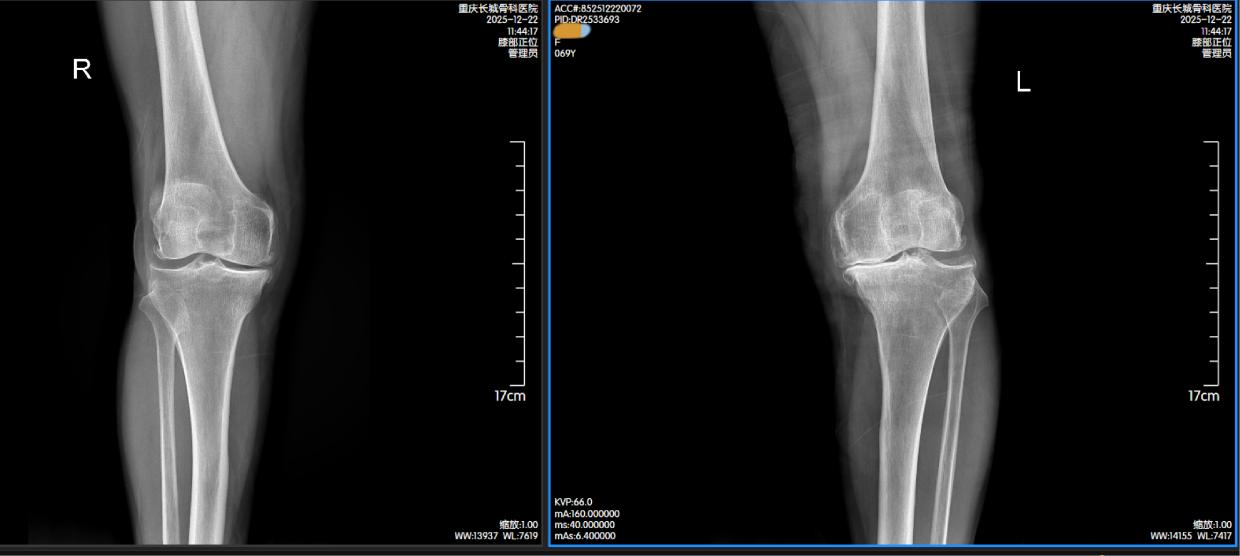

一次偶然的机会,黎婆婆的女儿得知同村一位阿姨去年在重庆长城骨科医院接受了髋关节置换手术,术后恢复效果非常好。抱着一丝希望,她立即带着黎婆婆前往该院就诊。经门诊详细检查后,黎婆婆被确诊为“单侧膝关节骨性关节病”,收入关节外科接受进一步治疗。

检查结果显示“单侧膝关节骨性关节病”。图源 重庆长城骨科医院

“骨性关节炎是中老年人群常见的慢性退行性疾病,核心病理变化是软骨破坏,常伴随软骨下骨硬化、囊性变和骨赘形成。”重庆长城骨科医院关节外科主任詹学锋介绍,该疾病多累及膝关节、髋关节等负重关节,病理变化最初发生于软骨,后续会逐渐侵犯软骨下骨板及滑膜等周围组织,临床表现为关节疼痛、变形及功能受限,严重影响患者生活质量。